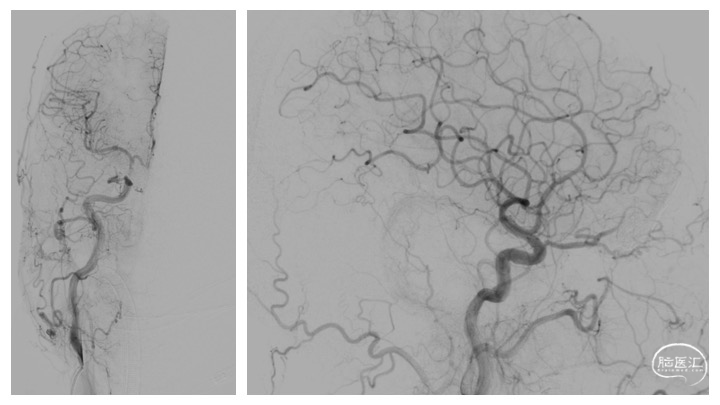

图1.当地医院CT及磁共振检查结果因故未能提供,仅提供右侧颈内动脉造影。正侧位造影显示前颅底硬脑膜动静脉瘘,右侧眼动脉参与供血,经额叶皮层静脉及额底静脉分别向矢状窦及直窦引流,引流静脉迂曲扩张。

根据病史及入院辅助检查,诊断前颅底硬脑膜动静脉瘘明确。入院后完善脑血管造影检查(图2),便于进一步分析血管构筑,制定手术策略。

详细分析患者瘘口的血管构筑学(图3),术者认为经静脉途径的优势在于:相对于动脉途径,微导管经静脉途径能够确切地到达瘘口。且该患者的引流虽经皮层及额底内侧静脉分别向矢状窦及直窦引流,但两支引流静脉均起源于一短段的引流静脉。虽然皮层引流静脉有两处走行纤细,但根据术者既往的经验,微导管通过此处并不十分困难。术中同时穿刺右侧股动脉及股静脉,将造影导管超选至右侧颈总动脉,用于实时造影、三维血管构筑分析及路图指导。同时,将Neuronmax长鞘引导至右侧横窦,6F银蛇中间导管引导至上矢状窦中份。在路图指导下,Echelon-10导管经由矢状窦-右侧额叶皮层静脉途径成功超选至右侧额底引流静脉开口,在此处放置弹簧圈,用于防止Onyx逃逸,导致静脉窦栓塞或肺栓塞,随后在静脉端使用逆向高压锅技术,注入Onyx胶,完全栓塞瘘口(图4、5)。